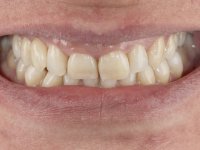

Female patient, 43 years old, non-smoker. Showed an edentulous space in the upper right canine area, resulting from tooth 1.3 impaction. The space had a mesio-distal diameter reduced to the normal size of the upper canine. This is consistent with the presence in the arch of the deciduous canine up to two years ago). Orthopantomography allows clearly view of tooth 1.3 impaction.The patient has a thick gingival phenotype and tolerable oral hygiene.

The patient wanted to "replace a milk tooth that fell” and would like a fixed tooth, but did not want to extract the impacted tooth, nor to place an implant.